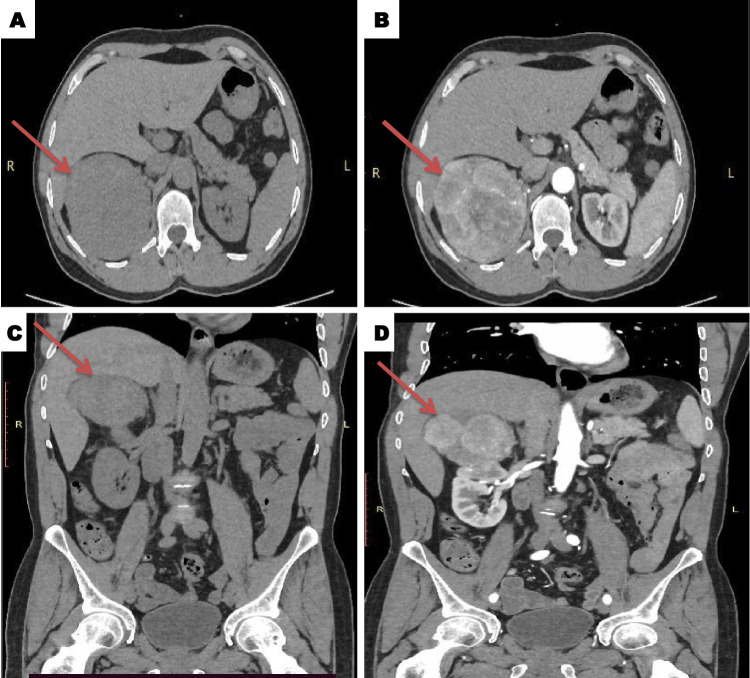

Case presentation: A 56-year-old male presented with severe uncontrolled hypertension accompanied by persistent headaches and palpitations and was unresponsive to standard anti-hypertensive therapy. Clinical examination revealed a palpable mass in the right flank. Abdominal computed tomography revealed a large, heterogeneous mass (approximately 10 cm) occupying the hepatorenal space, which was initially suggestive of pheochromocytoma. Due to limited diagnostic resources, confirmatory biochemical testing was unavailable. The patient underwent radical nephrectomy and histopathology confirmed clear cell RCC (WHO/ISUP grade 2). The patient's hypertension resolved completely postoperatively, with subsequent follow-ups demonstrating stable blood pressure and no metastatic disease.